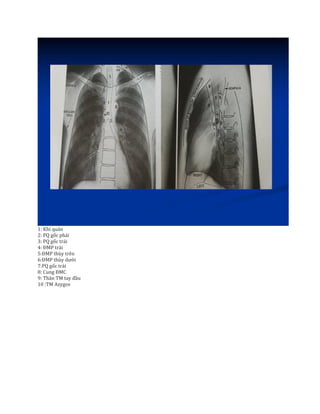

– Các cấu trúc bình thường trong lồng ngực .

1: Khí quản

2: PQ gốc phải

3: PQ gốc trái

4: ĐMP trái

5:ĐMP thùy trên

6:ĐMP thùy dưới

7:PQ gốc trái

8: Cung ĐMC

9: Thân TM tay đầu

10 :TM Azygos

– Các cấutrúc bình thường trong lồng ngực .

1: Khí quản 2:PQ gốc phải 3: PQ gốc trái 4: ĐMP trái 5:ĐMP thùy trên 6:ĐMP thùy dưới 7:PQ gốc trái 8: Cung ĐMC 9: Thân TM tay đầu 10 :TM Azygos